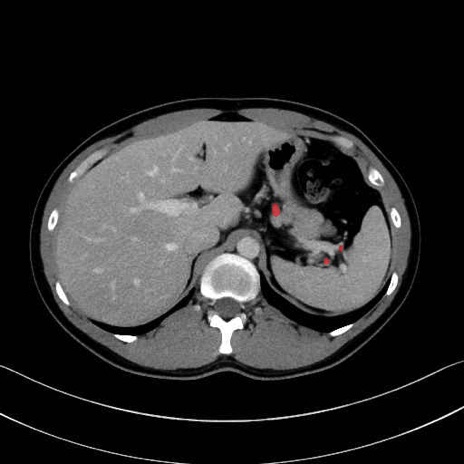

【症例】20歳代 男性 スクリーニング

■起始:典型的には腹腔動脈幹(celiac trunk)から左胃動脈・総肝動脈とともに三分岐し、脾動脈は左後上方へ向かう。

■走行:膵上縁または膵実質背側を蛇行しながら左方へ進み、膵尾部近傍で脾門へ至る。蛇行の程度は個体差が大きい。

■終枝:脾門部で複数の終末枝に分かれ、上極・下極枝や脾門枝群を形成する。胃短動脈群や左胃大網動脈はしばしば脾動脈から分岐する。